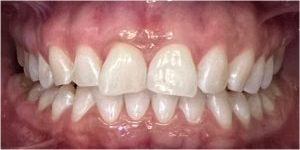

Dzięki precyzyjnej diagnostyce, doktor Magdalena Zawirska opracowała kompleksowy plan leczenia, który obejmował: stomatologię zachowawczą, periodontologię i protetykę stomatologiczną. Zastosowano licówki i korony pełnoceramiczne, przeprowadzając kompleksową rekonstrukcję zwarcia.

Pacjentka może się teraz cieszyć się pięknym i zdrowym uśmiechem